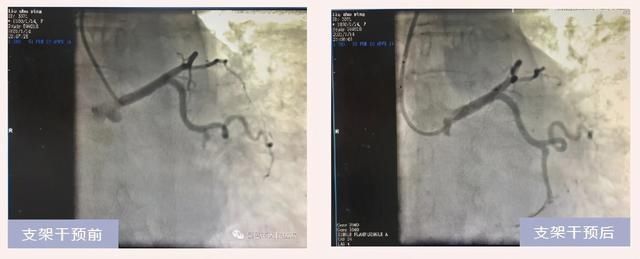

急诊冠脉造影示回旋支远段闭塞,立即给予球囊扩张、冠脉支架植入术,患者胸痛明显缓解,手术仅用时45分钟!